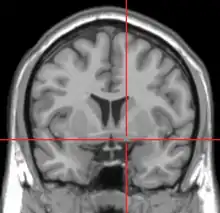

La substantia innominata dite aussi « substance innominée de Reichert » désigne la partie du cerveau au sein du prosencéphale basal constituée d'un ensemble mal défini de structures incluant le noyau basal de Meynert et une partie du striatopallidum ventral (dont le noyau accumbens), d'une part et une partie du complexe amygdalien d'autre part.